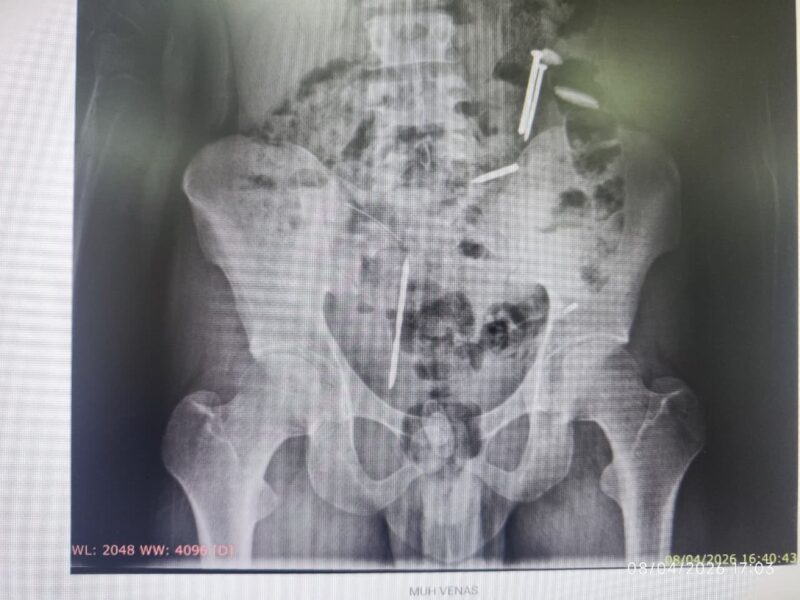

MVA, yang sebelumnya terpaksa dipasung keluarga karena perilaku agresif, menjalani prosedur rontgen sebagai syarat pemeriksaan kesehatan. Hasil pemindaian tersebut menunjukkan pemandangan memilukan; benda-benda asing terlihat jelas bersarang di rongga perutnya.

Hasil rontgen menunjukkan adanya benda tajam menyerupai paku dan potongan logam lainnya. Secara detail, ada dua benda diduga paku dan tiga benda logam yang bersarang di sana,” papar Roni dengan nada prihatin.

Selain logam, tim medis juga mendeteksi adanya gumpalan misterius berwarna hitam. Belum bisa dipastikan apakah itu massa darah yang membeku atau material asing lain seperti plastik, yang menurut penuturan keluarga, kerap dikonsumsi oleh MVA dalam kondisi tidak sadar.